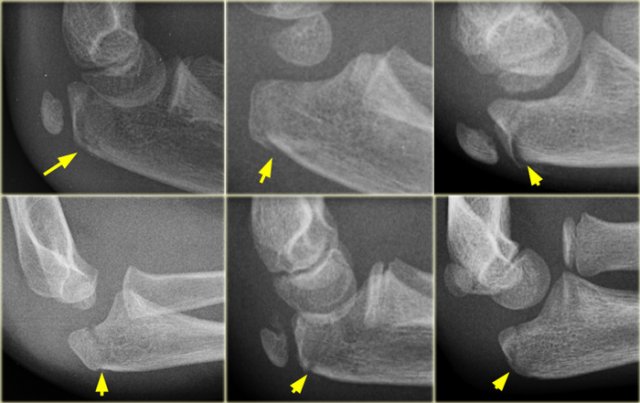

Olecranon fractures (3)

On the left some examples of fractures of the olecranon.

Notice how subtle some of these fractures are.

Olecranon fracture indicated by discontinuity of the dorsal cortex. No associated fracture. Olecranon fracture indicated by discontinuity of the dorsal cortex. No associated fracture.

Olecranon fractures

Olecranon fractures in children are less common than in adults. As discussed above they are associated with radial neck fractures and radial dislocations.

Normal olecranon ossification centres in a patient with a tilted radial neck fracture. Normal olecranon ossification centres in a patient with a tilted radial neck fracture.

Olecranon fractures (2)

Do not mistake the apophysis or its separate ossification centres for a fracture.

The apophysis has undulating faintly sclerotic margins.

The growth plate usually has a different oblique course compared to a fracture-line.